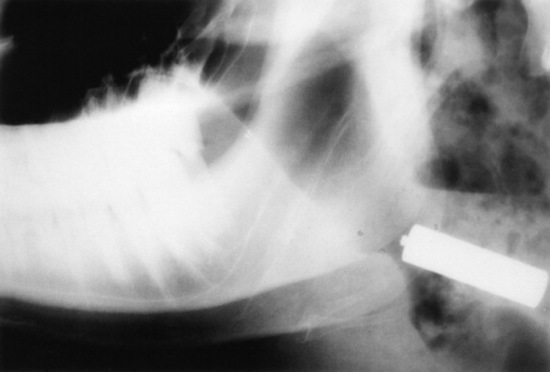

Trephine sites for sinusotomy (Fig. 31-47) are as follows:

1 Dorsal frontal sinus

2 Postorbital diverticulum

3 Rostral frontal sinus

4 Turbinate portion of the frontal sinus

5 Maxillary sinus

image

Fig. 31-47 Trephine sites for sinusotomy. A, Dorsal frontal sinus. B, Postorbital diverticulum. C, Rostral frontal sinus. D, Turbinate portion of frontal sinus. The maxillary sinus is trephined ventral to a line from the infraorbital foramen to the medial canthus (arrowhead). If draining tracts are present at the poll, an additional sinusotomy can be made in the cornual portion of the frontal sinus (arrowhead).

Cattle that have frontal sinusitis after dehorning should be treated by sinusotomy and drainage of the sinus.53 Sinusotomy sites should be based on anatomic landmarks51 and modified as needed to accommodate any frontal bone distortion or wounds related to dehorning.51 Sinusotomy should be performed 3 to 4 cm from midline, intersecting a line drawn between the caudal aspect of the orbits. If draining tracts are present at the poll, an additional sinusotomy can be made in the cornual portion of the frontal sinus.51 Sinusotomy is performed after sedation and local anesthetic infiltration of the centesis site(s). A 2-cm—diameter circular piece of skin is excised, and a 19-mm (¾-inch) trephine used to create an opening into the sinus, through which purulent fluid should be evacuated and the sinus lavaged.

Additional trephine sites that permit access to other regions of the frontal sinus include the postorbital diverticulum, which is trephined approximately 4 cm caudal to the dorsal rim of the orbit, just above the temporal crest of the frontal bone; the rostral frontal sinus, which is trephined just caudal to a line between the centers of the orbits and to either side of the midline; and the turbinate portion of the frontal sinus, which is trephined just rostral to the line described and to either side of the midline.

Access to the maxillary sinus is achieved by trephining ventral to a line from the infraorbital foramen to the medial canthus. If an infected tooth is the cause of maxillary sinusitis, a sinusotomy is created with a trephine over the affected tooth to repel it; otherwise, the hole is usually made just dorsal and caudal to the facial tuberosity. The trephine site should be higher in the sinus of younger animals because the tooth roots are longer.